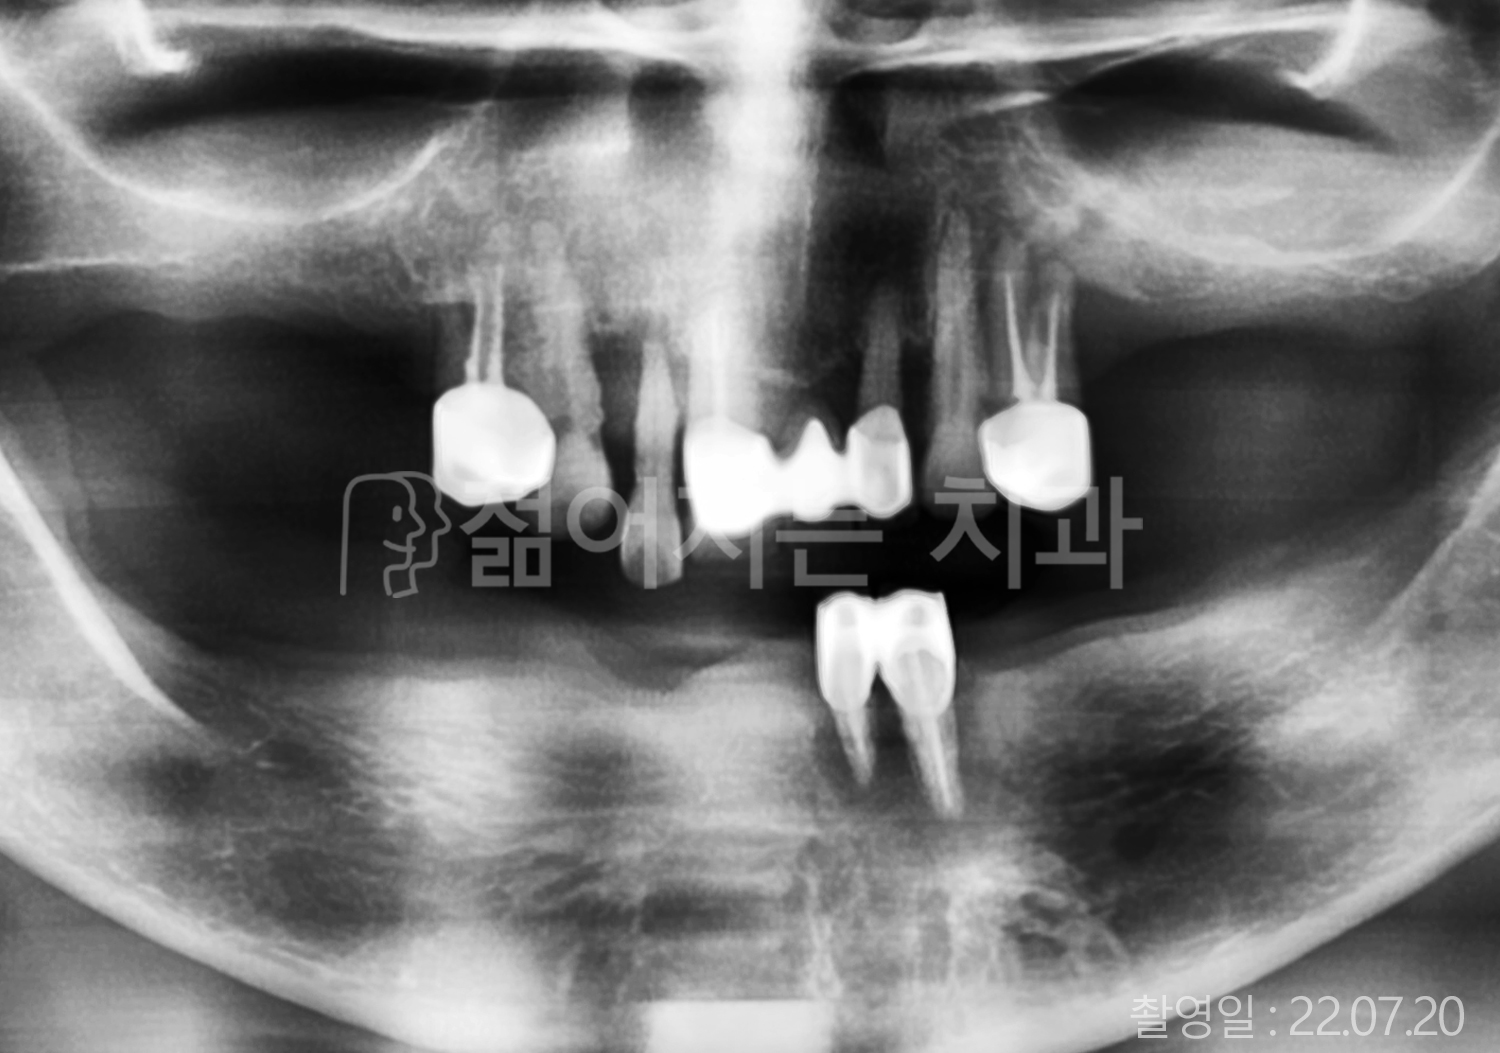

• 60대 고혈압, 고지혈증 전체치아 10개 이상 임플란트

• 70대 전체치아 10개 이상 임플란트

• 60대 전체치아 10개 이상 임플란트

• 50대 전체치아 10개 이상 임플란트

• 50대 고혈압, 고지혈증 전체치아 10개 이상 임플란트

• 60대 고혈압, 당뇨, 고지혈증 전체치아 10개 이상 임플란트

• 80대 고혈압, 당뇨, 골다공증 전체치아 10개 이상 임플란트

• 60대 고혈압 전체치아 10개 이상 임플란트

• 60대 고지혈증 전체치아 10개 이상 임플란트

• 60대 당뇨 전체치아 10개 이상 임플란트